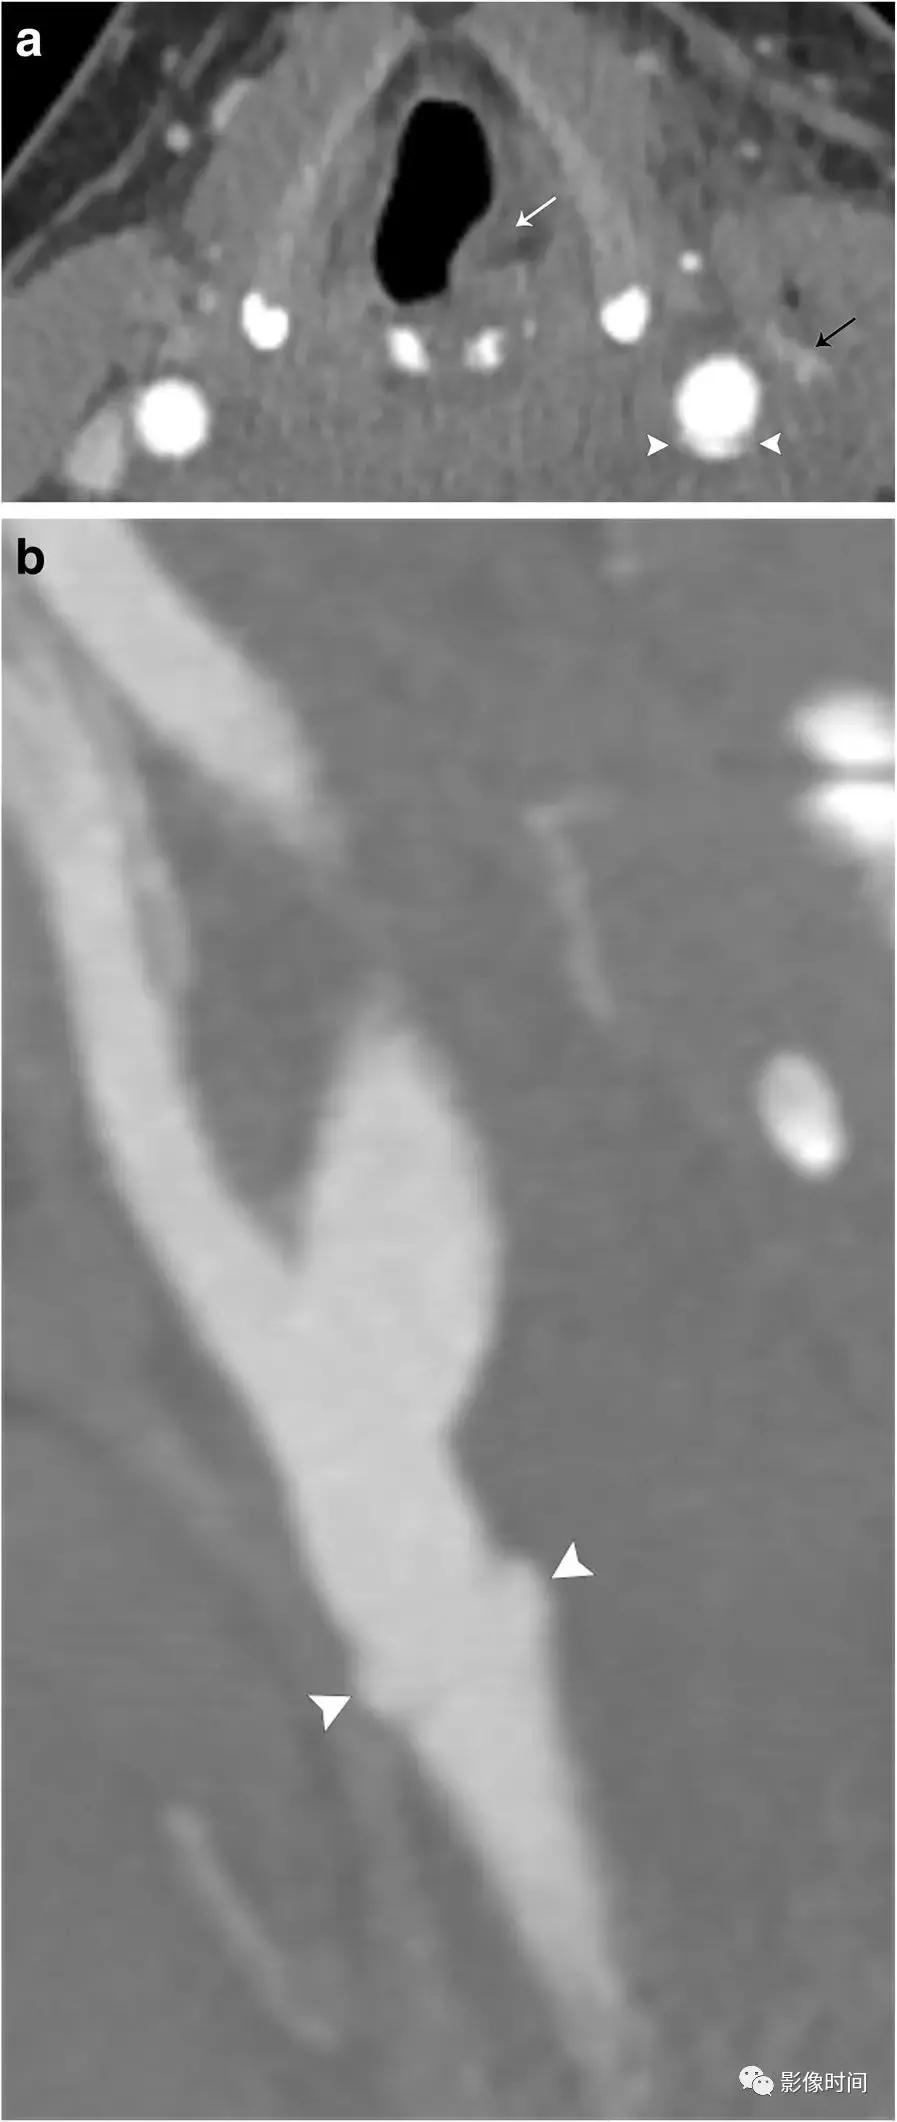

5、颈内动脉/颈总动脉假性动脉瘤:假性动脉瘤发生在内膜和中膜受到损伤时,导致仅由外膜层所包含的血肿。通常是无症状,而且是偶然发现的;然而,却有很大的破裂风险,死亡率很高。假性动脉瘤可由于创伤、血管炎、感染或为医源性。CTA 显示血管壁不规则外凸影。T1WI 脂肪抑制序列能够评估腔内血栓和假性动脉瘤的大小。DSA 仍是评价假性动脉瘤的金标准。

模式图显示内膜及中膜撕裂,外膜包裹血肿,CTA 显示动脉壁不规则状外凸影。a. CTA 显示刺伤后左侧颈总动脉(箭头)的不规则外凸影。左颈内静脉也受伤(黑色箭头)。左侧声带麻痹 (白色箭头),因伴有迷走神经损伤。b. 矢状曲面重建 CTA 更好地显示局灶性假性动脉瘤位于左颈总动脉分叉近端。